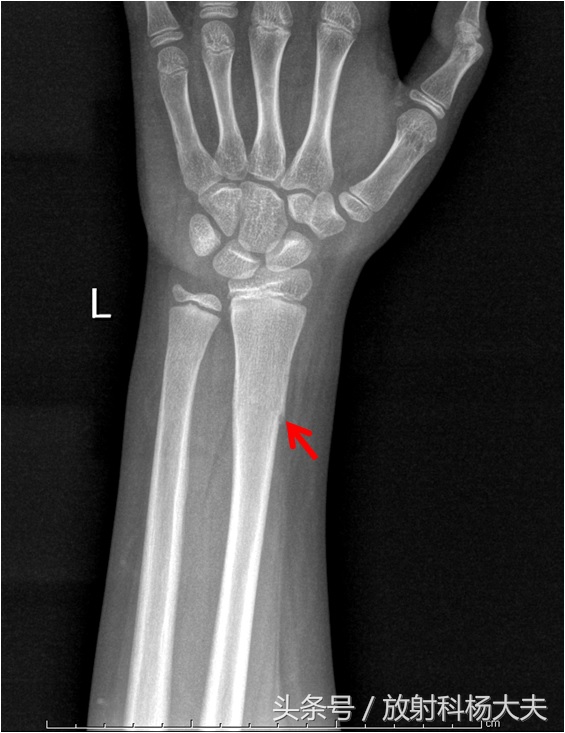

这是一个11岁孩子的青枝骨折。红箭所示的地方翘起来一点,就是骨折的部位。

老王的大孙子桡骨远段骨皮质有翘起,而并没有完全的骨质中断。我们称这种骨折为青枝骨折,因为没有明显的骨折线,骨折端也没有移位,有时候甚至仅仅表现为局部骨皮质的皱褶。因此这类骨折很容易漏诊。形成这种现象的原因在于儿童的骨骼中含有较多的有机物,外面包裹的骨外膜由特别的厚,因此在力学上就具有很好的弹性和韧性,不容易折断,遭受*力暴**发生骨折就会出现与植物青枝一样折而不断的情况。就好像植物的青嫩枝条,撅一下可听到里边折断的声音, 但是还连着一样。青枝骨折时,骨骼虽“折”却仍然未“断”,因而一般都属于稳定骨折,治疗起来也相对简单,通常是不需要手术治疗的,只要用石膏外固定治疗都有很好的效果。